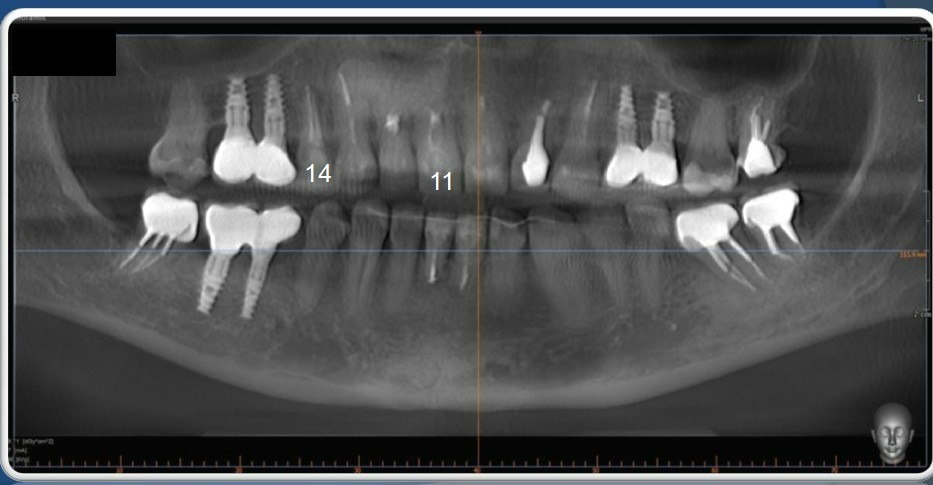

Жалобы были скромные — на периодические ноющие боли в области 11 зуба (центральный верхний зуб справа). Но при диагностике была выявлена серьезная проблема — трещина корня. Увы подобный диагноз не предполагает другого решения проблемы, кроме удаления. Также был диагностирован хронический периодонтит на 14 зубе (верхний правый сегмент зубного ряда, так же попадает в видимую зону при улыбке). Премоляр был ранее лечен по поводу периодонтита, но к сожалению консервативное лечение оказалось неэффективно. Ситуация также осложнялась тем, что ранее пациентке проводилось эндодонтическое лечение 11,12 зубов с последующей резекцией верхушек корней и удалением крупной радикулярной кисты, занимавшей почти весь объем костной ткани в области 11,12,13 зубов и до полости носа.

Сопоставление в специальной программе данных компьютерной томографии и цифрового скана зубов.

С учетом данных компьютерной томографии я отмоделировал и распечатал на 3D принтере: хирургический шаблон, который позволил установить имплантаты в наиболее правильной позиции с учетом всех анатомических особенностей строения челюсти и зубного ряда, а так же временные коронки.